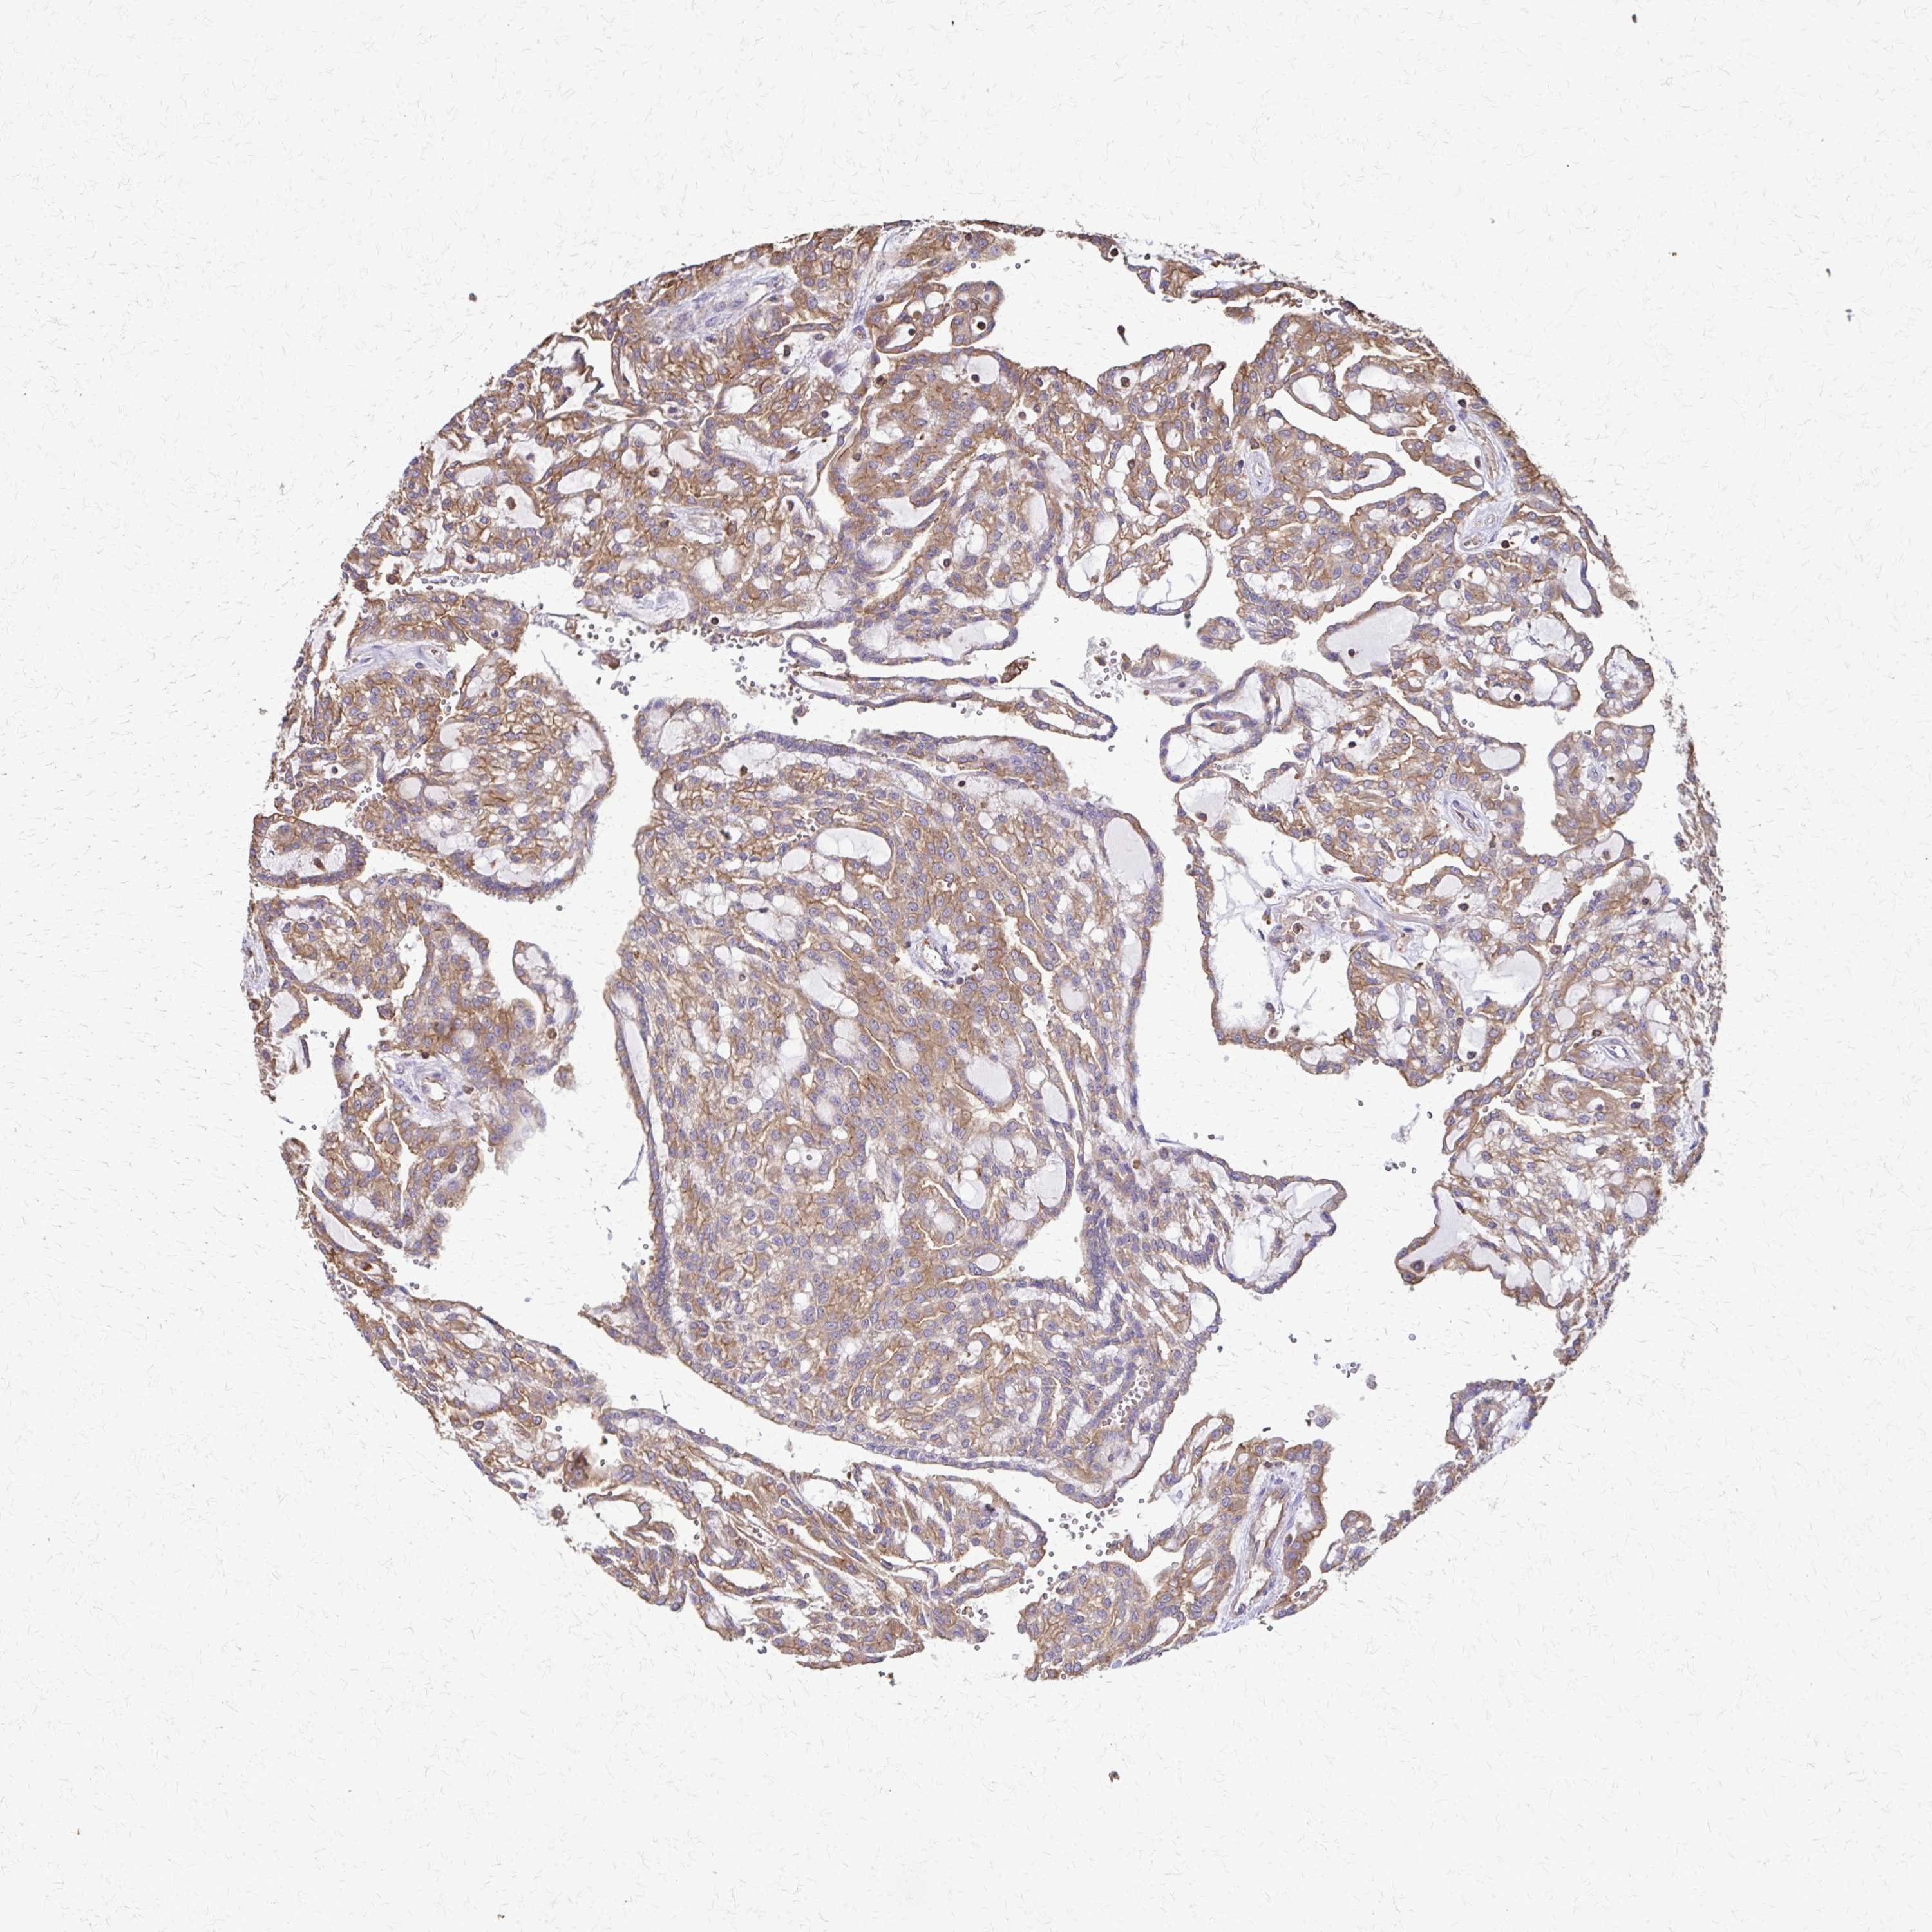

KIDNEY RENAL CLEAR CELL CARCINOMA (VALIDATION) - Interactive survival scatter ploti

The Survival Scatter plot shows the clinical status (i.e. dead or alive) for all individuals in the patient cohort, based on the same data that underlies the corresponding Kaplan-Meier plots. Patients that are alive at last time for follow-up are shown in blue and patients who have died during the study are shown in red.

The x-axis shows the expression levels (FPKM) of the investigated gene in the tumor tissue at the time of diagnosis. The y-axis shows the follow-up time after diagnosis (years). Both axes are complimented with kernel density curves demonstrating the data density over the axes. The top density plot shows the expression levels (FPKM) distribution among dead (red) and alive patients (blue). The right density plot shows the data density of the survived years of dead patients with high and low expression levels respectively, stratified using the cutoff indicated by the vertical dashed line through the Survival Scatter plot. This cutoff is automatically defined based on the FPKM cutoff that minimizes the p-score. The cutoff can be changed by dragging the vertical line or by entering a cutoff value in the square labeled "Current cut-off".

Under the Survival Scatter plot the p-score landscape (black curve; left axis) is shown together with dead median separation (red curve; right axis). Dead median separation is the difference in median mRNA expression between patients who have died with high and low expression, respectively. It is calculated as follows: median FPKM expression of dead patients with high expression - median FPKM expression of dead patients with low expression. This is intended to aid the user in visually exploring custom cutoffs and the associated p-scores and dead median separation.

Individual patient data is displayed and can be filtered by clicking on one or more of the category buttons on the top of the page. Categories describing expression level and patient information include: high, low, alive, dead, female, male and tumor stages. The scale of the x-axis can be toggled between linear and log-scale by clicking on the "x log" button. Mouse-over function shows TCGA ID, patient information and mRNA expression (FPKM) for each patient.

& Survival analysisi

Kaplan-Meier plots summarize results from analysis of correlation between mRNA expression level and patient survival. Patients were divided based on level of expression into one of the two groups "low" (under cut off) or "high" (over cut off). X-axis shows time for survival (years) and y-axis shows the probability of survival, where 1.0 corresponds to 100 percent.

EEF2 is not prognostic in Kidney Renal Clear Cell Carcinoma (validation)

Best expression cut offi

Based on the FPKM value of each gene, patients were classified into two groups and association between prognosis (survival) and gene expression (FPKM) was examined. The best expression cut-off refers the FPKM value that yields maximal difference with regard to survival between the two groups at the lowest log-rank P-value. Best expression cut-off was selected based on survival analysis .

When clicking on this number, the vertical dashed line indicating cut-off, the interactive survival plot, and the Kaplan-Meier curve will be adjusted to show results based on the best expression cut-off.

: 914.34

TCGA RNA samplesi

RNA-seq data is reported as average FPKM (number Fragments Per Kilobase of exon per Million reads), generated by the The Cancer Genome Atlas (TCGA) .

Normal distribution across the dataset is visualized with box plots, shown as median and 25th and 75th percentiles. Points are displayed as outliers if they are above or below 1.5 times the interquartile range. FPKM values of the individual samples are presented next to the box plot.

Average pTPM 1279.4

Number of samples 100